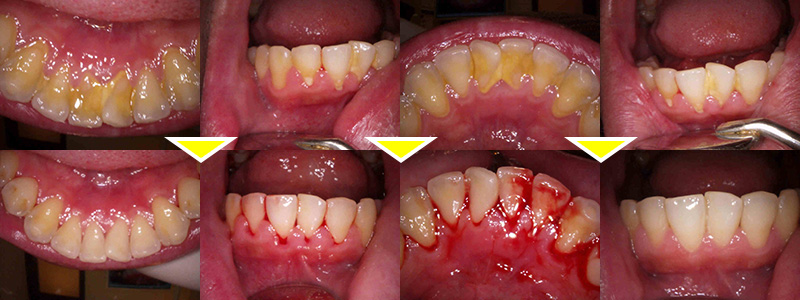

クリーニングをはじめとした予防処置においては、歯科衛生士が専門的な視点でお口全体を丁寧にチェックし、歯ぐきの状態や歯周病の兆候、わずかな変化も見逃しません。これにより、病気の早期発見・早期対応へとつなげることが可能になります。